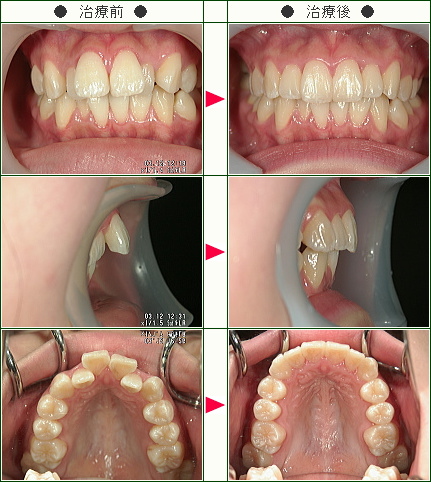

☆出っ歯矯正症例(A・H様 17歳 女性)

治療解説

主訴は前歯の前突感(出っ歯)の改善です。

まずはワイヤーを使用して右上のデコボコを改善していきます。

ワイヤーの使用期間が約3か月で、マウスピースを3か月使用して歯並びを内側に傾斜して治療していきました。

トータルでの治療期間は6ヵ月で、調整料金を含めたトータルの治療費は29万円です。

上側だけの部分矯正では、噛み合わせは変わりませんので、見た目の改善だけの審美治療になります。

部分矯正において、ワイヤーでデコボコを改善するだけだと、矯正前よりも少しだけ前方に出てしまうため、歯の隣接面を少し削ることで前歯の前突感を改善していきます。

どこまで前歯を中に入れたいかで、隣接面を削る量は患者様の判断で決まります。

歯を削らないでデコボコを治すだけですと、デコボコのある上の左右の1番目と上の2番目の間にブラックトライアングルという隙間が残るために、ブラックトライアングルを減らすためにもその部分の隣接面を削ってブラックトライアングルを改善していきます。